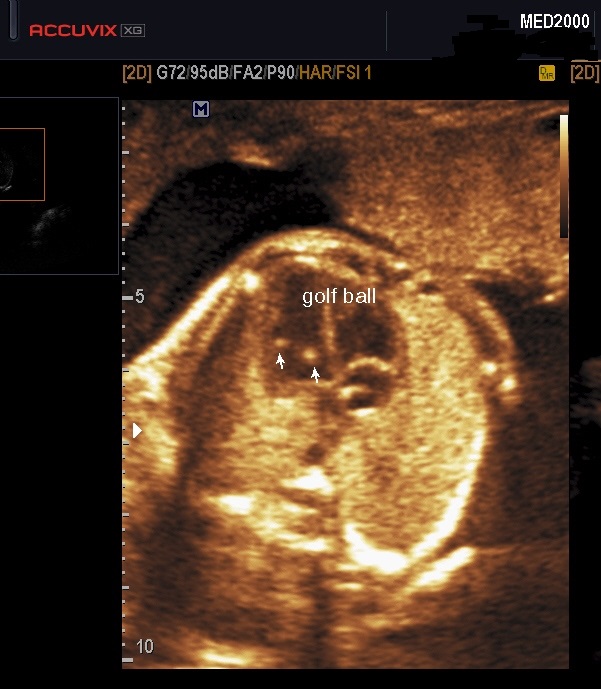

La Golf Ball è una piccola struttura ad ecogenicità comparabile con quella dell'osso fetale tipicamente presente all'interno dei ventricoli nella regione del muscolo papillare o delle corde tendinee che si muove in sincronia con la valvola mitrale o tricuspide ma non interessa la parete ventricolare (Wax JR et al., 2000; Carriço A et al., 2004; Arda S et al, 2007;  Lorente AMR et al, 2017). Per ridurre i falsi positivi legati al fatto che i muscoli papillari sono spesso visibili come punti ecogenici è utile ridurre il gain per assicurarsi che il FEI non svanisca prima  dell'ecogenicità delle costole (Bethune M. et al., 2007).

Ecograficamente  si osserva in sezione quattro camere apicale (100%) come una piccola formazione ecogena di diametro variabile da 1 a 4 mm. (Wax JR et al., 2000;  Arda S et al, 2007 ).  E' più frequente nel ventricolo sinistro (92%), meno frequente nel ventricolo destro (4%) o bilateralmente (4%)( Wei M et al., 2018); rare sono la localizzazione intra-atriale o come foci diffusi (Wax JR et al., 2000;  Arda S et al, 2007; ).